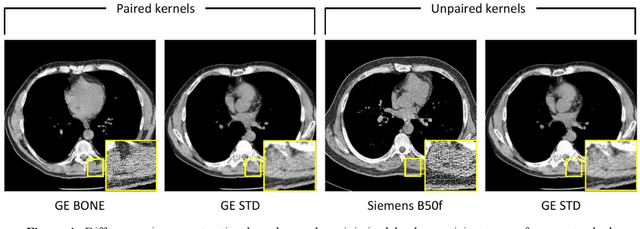

Abstract:The reconstruction kernel in computed tomography (CT) generation determines the texture of the image. Consistency in reconstruction kernels is important as the underlying CT texture can impact measurements during quantitative image analysis. Harmonization (i.e., kernel conversion) minimizes differences in measurements due to inconsistent reconstruction kernels. Existing methods investigate harmonization of CT scans in single or multiple manufacturers. However, these methods require paired scans of hard and soft reconstruction kernels that are spatially and anatomically aligned. Additionally, a large number of models need to be trained across different kernel pairs within manufacturers. In this study, we adopt an unpaired image translation approach to investigate harmonization between and across reconstruction kernels from different manufacturers by constructing a multipath cycle generative adversarial network (GAN). We use hard and soft reconstruction kernels from the Siemens and GE vendors from the National Lung Screening Trial dataset. We use 50 scans from each reconstruction kernel and train a multipath cycle GAN. To evaluate the effect of harmonization on the reconstruction kernels, we harmonize 50 scans each from Siemens hard kernel, GE soft kernel and GE hard kernel to a reference Siemens soft kernel (B30f) and evaluate percent emphysema. We fit a linear model by considering the age, smoking status, sex and vendor and perform an analysis of variance (ANOVA) on the emphysema scores. Our approach minimizes differences in emphysema measurement and highlights the impact of age, sex, smoking status and vendor on emphysema quantification.